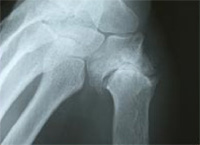

La rhizarthose c’est l’arthrose de la base du pouce. Elle atteint l’articulation entre le trapèze et le premier métacarpien. C’est un problème fréquent qui atteint particulièrement les femmes de la cinquantaine et souvent des 2 côtés à des stades cliniques et radiologiques différents. Parfois l’arthrose est la conséquence d’une fracture, d’un rhumatisme ou d’une infection. Mais le plus souvent la cause exacte de l’arthrose n’est pas connue. Elle est dite idiopathique.

Le symptôme habituel est la douleur, particulièrement dans les gestes de la vie quotidienne utilisant la pince pollici-digitale (c’est-à-dire le pouce avec un autre doigt) comme tourner une clé, ouvrir un bocal, ouvrir une fenêtre. Peu à peu, l’articulation se détériore puis se sub-luxe et apparaît alors une déformation caractéristique à la base du pouce.

Les radiographies de face et de profil du pouce (incidence de Kapandji) permettent de confirmer le diagnostic clinique et d’apprécier l’importance de la destruction articulaire et la conservation d’un certain volume osseux.

![]() |

Initialement, le traitement est toujours conservateur et médical associant le repos, les anti-inflammatoires, une attelle en plastique thermo formable sur mesure maintenant le pouce en bonne position, portée la nuit. La rééducation à visée antalgique et anti-inflammatoire (électrothérapie, ultra sons) et éventuellement une infiltration peuvent être tentées. Si ce traitement bien conduit pendant 6 mois à 1 an reste insuffisant, une intervention chirurgicale peut être envisagée. Deux grands types d’interventions sont proposés en fonction de l’âge, de la destruction de l’articulation, du travail et du côté dominant et des habitudes du chirurgien.

La trapézectomie consiste à ôter l’os malade. Pour stabiliser le pouce on associe le plus souvent une ligamentoplastie, c’est-à-dire l’utilisation d’un tendon du voisinage qui est faufilé à la base du premier métacarpien. La prothèse trapezo-métacarpienne. Cette prothèse ressemble à une mini-prothèse de hanche, avec une tête sphérique métallique qui s’articule dans une cupule trapézienne en polyéthylène ou en métal. La fixation des pièces prothétiques dans l’os fait appel soit à la régénération osseuse (prothèses non scellées) soit à du ciment (prothèses scellées).